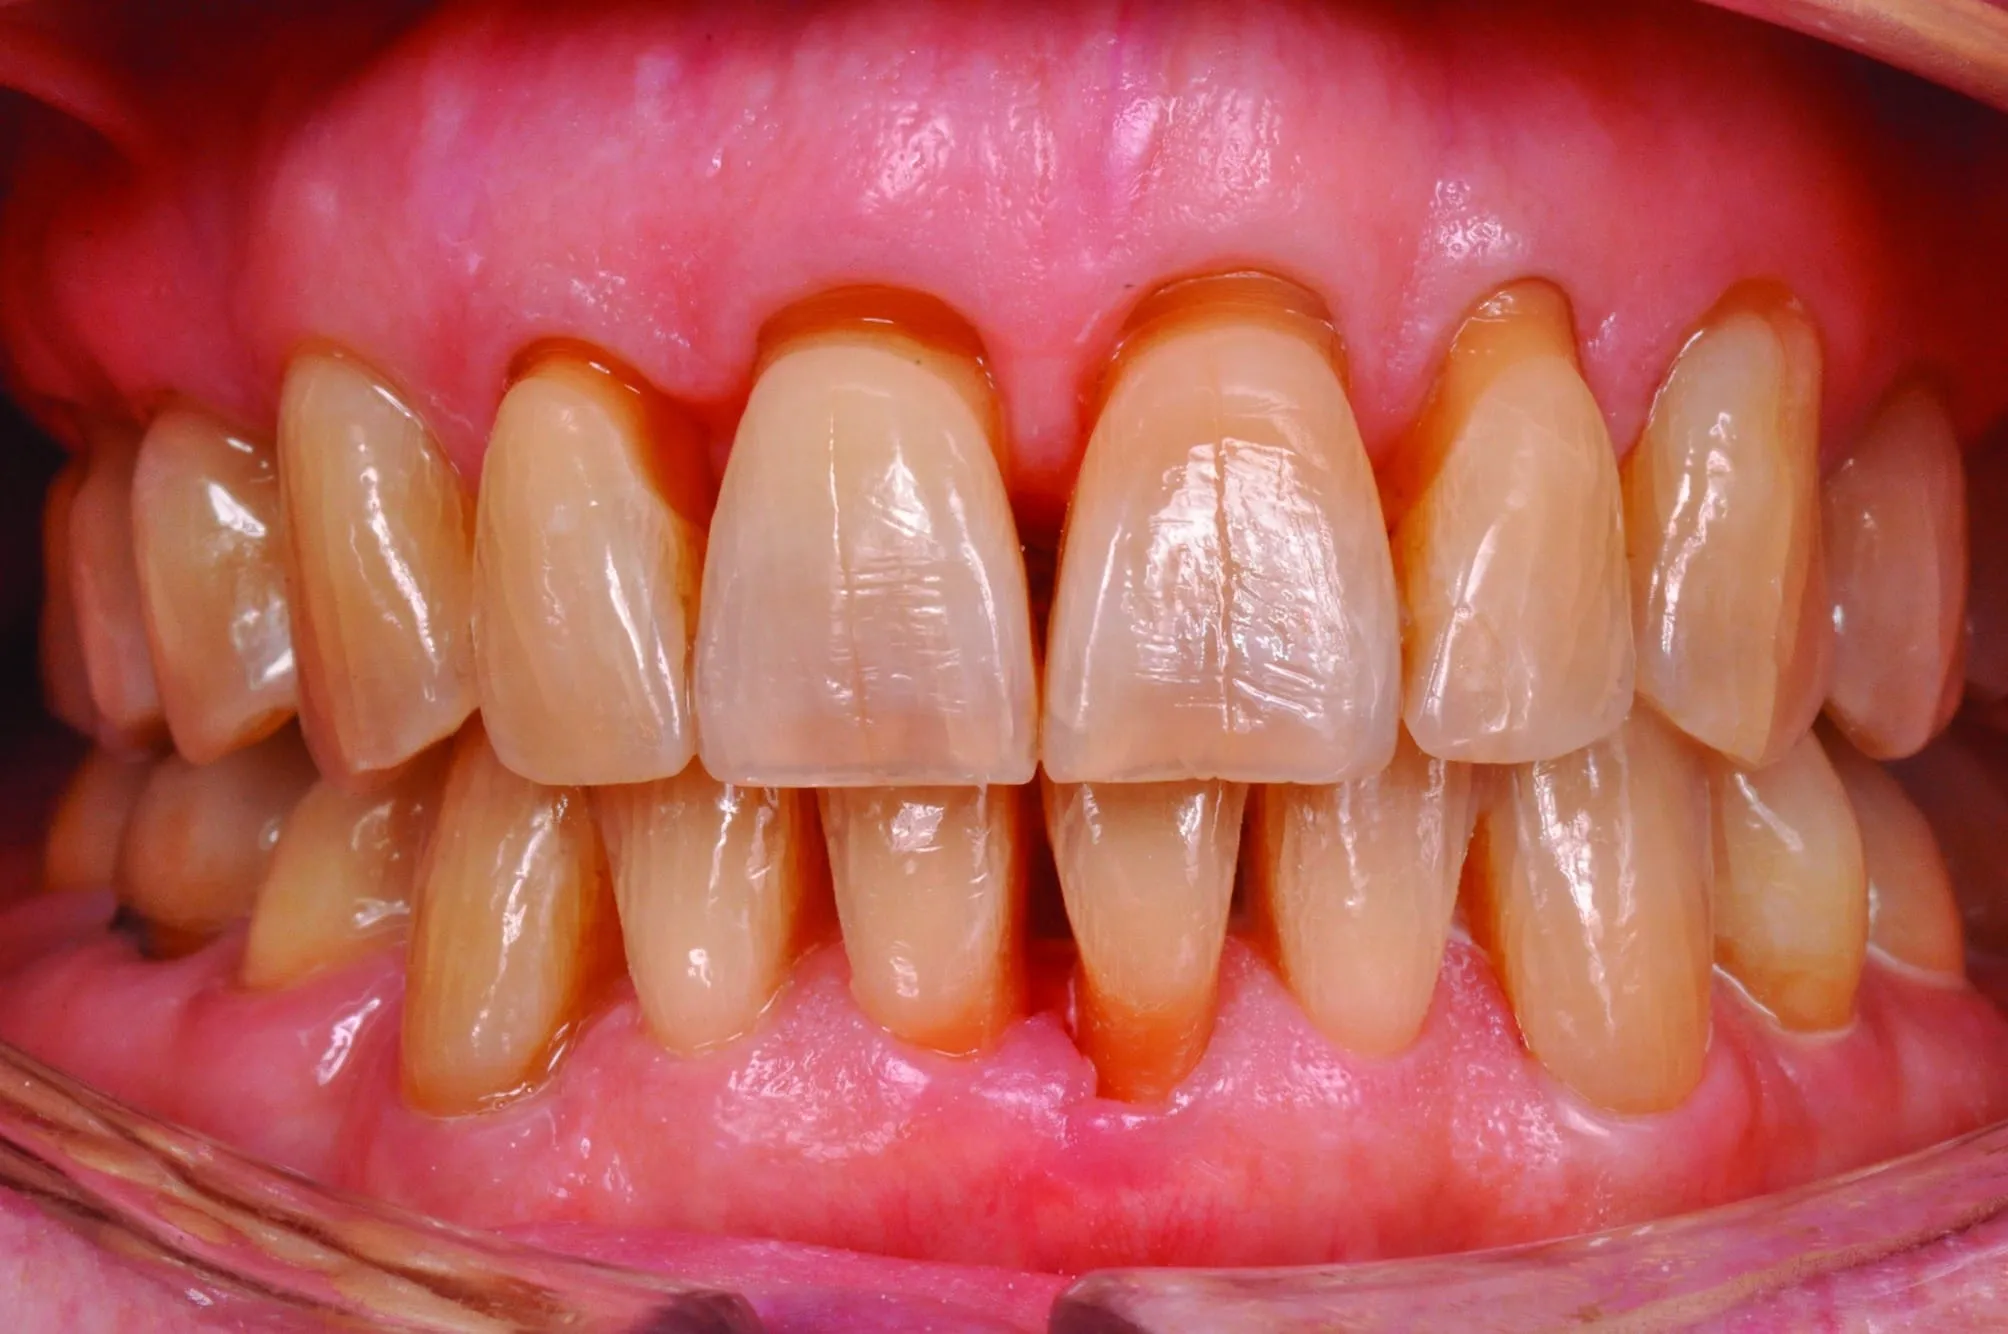

Greffes Gingivales

Corriger les récessions gingivales, renforcer les tissus fragiles et protéger les racines exposées.